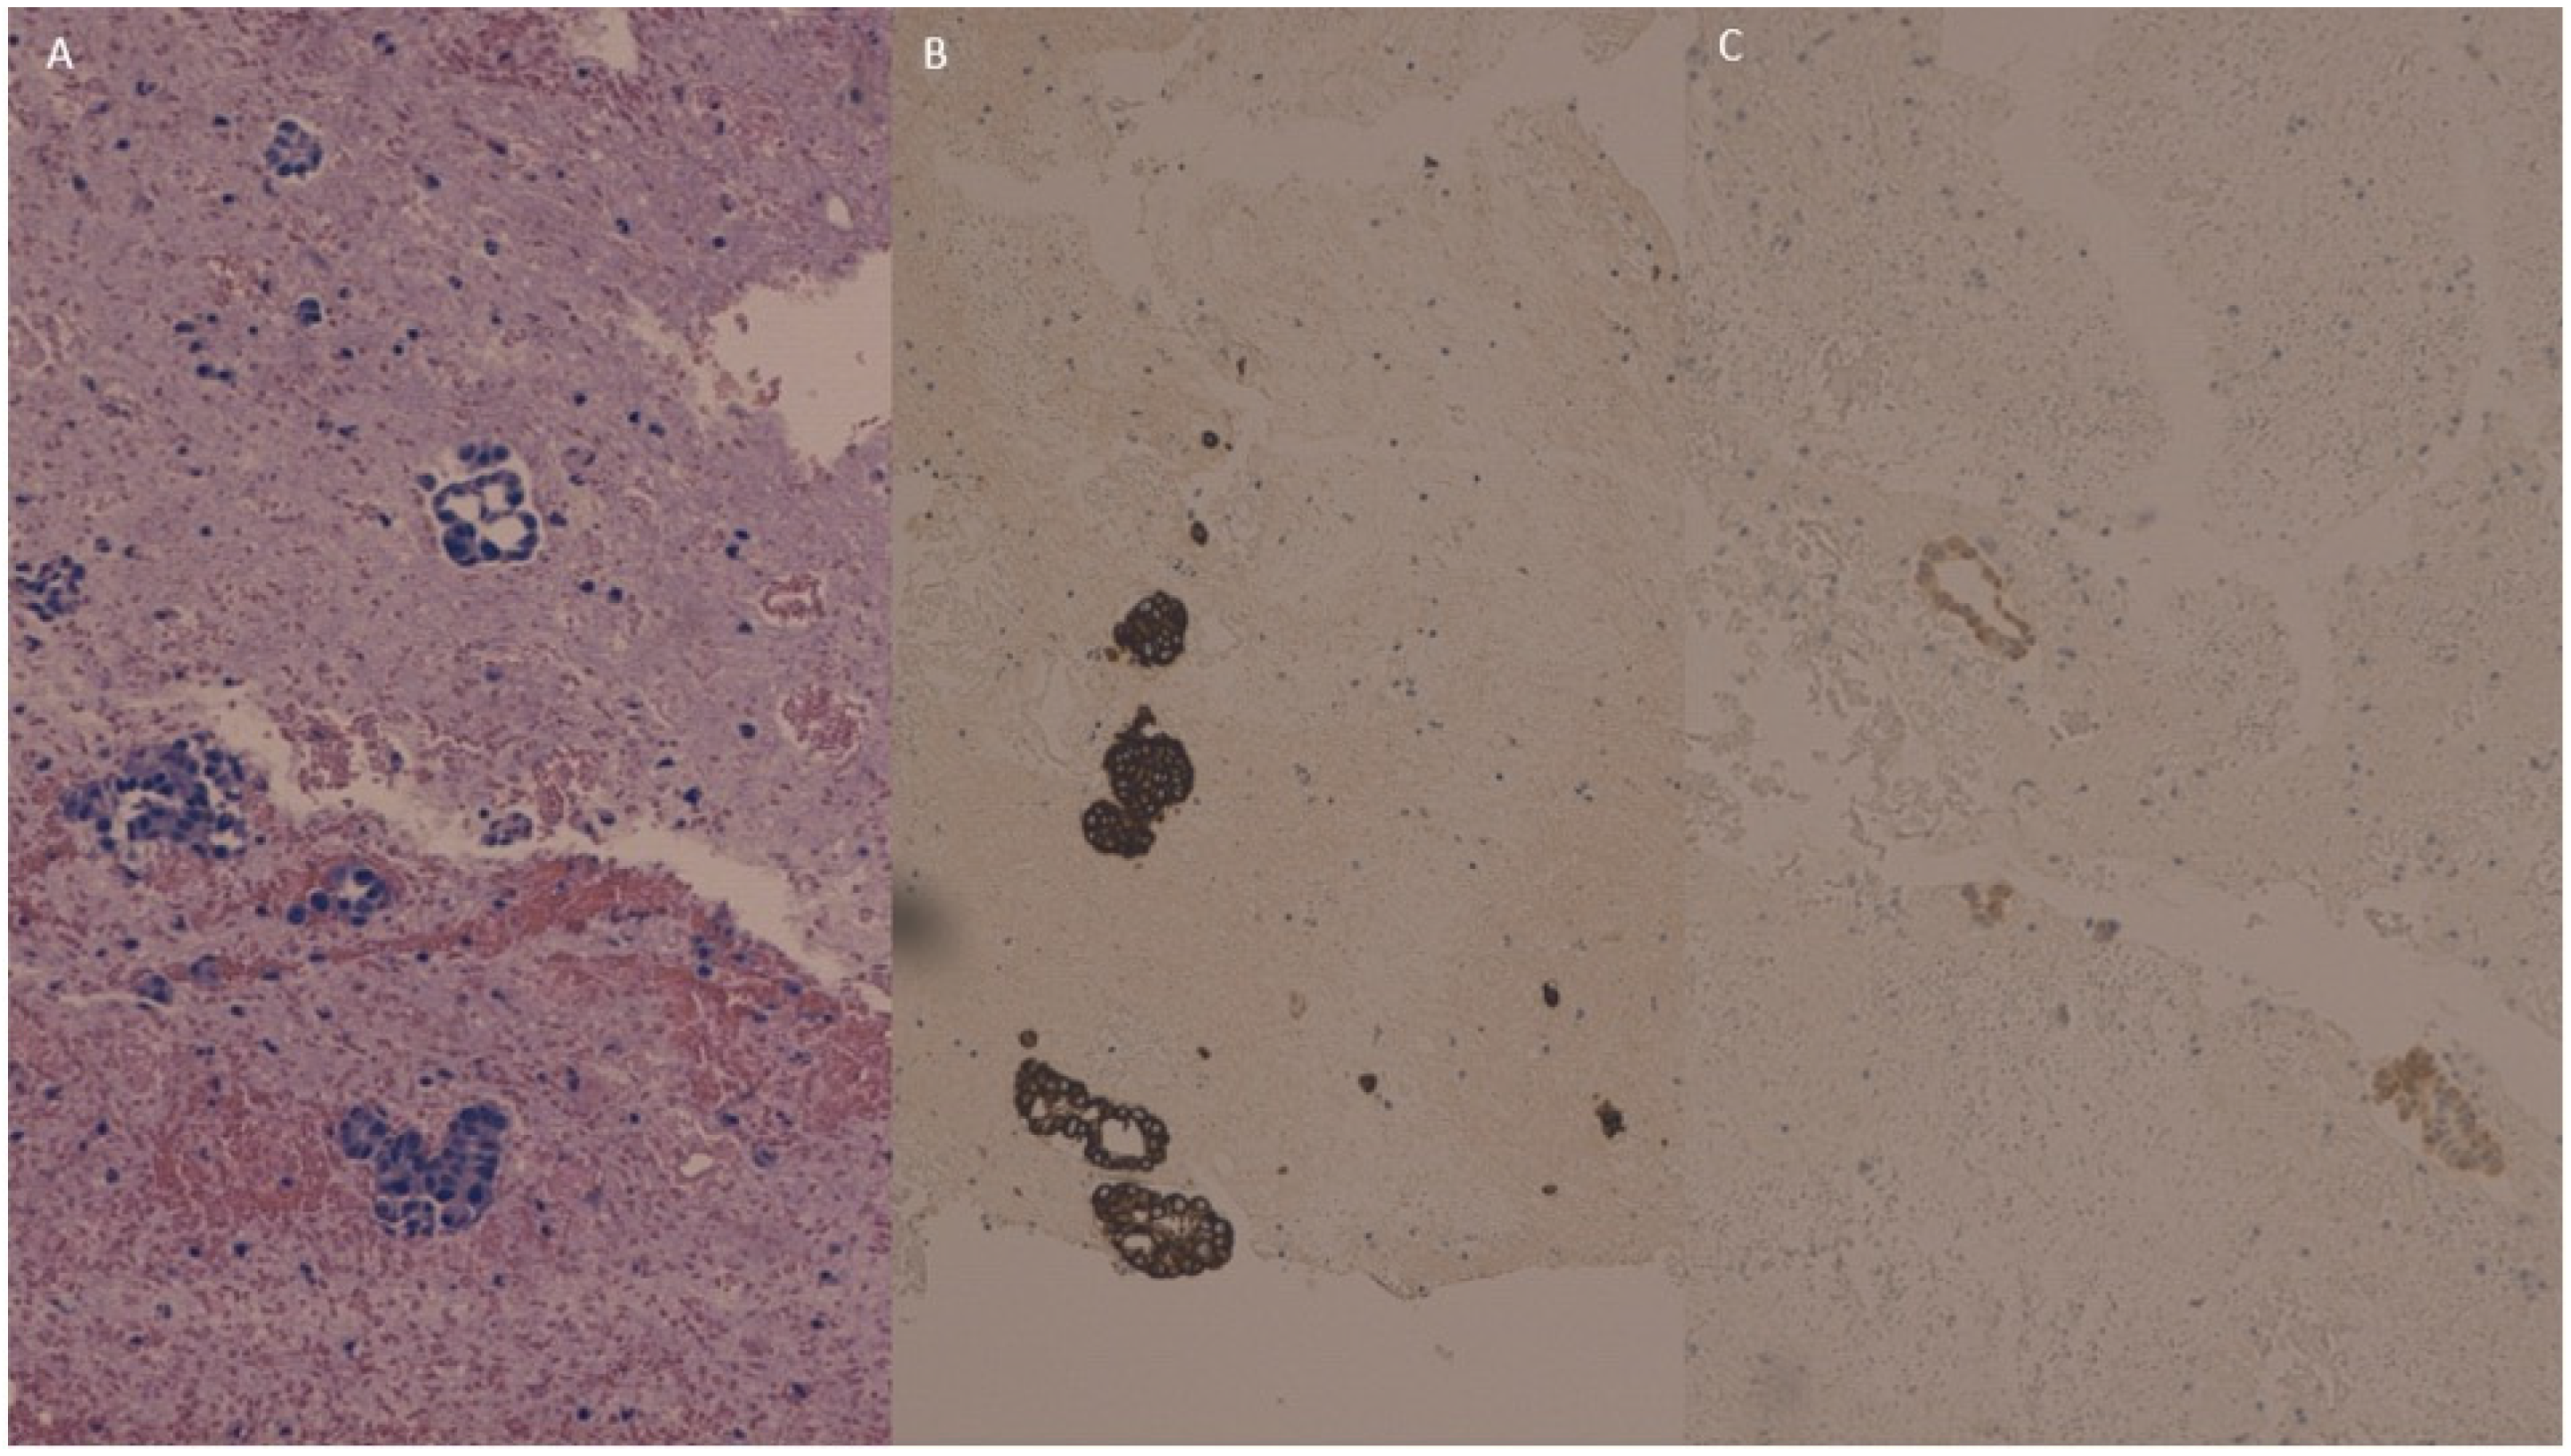

The ovarian metastasis from the gallbladder carcinoma (Figure 3A) was intensely and diffusely immunoreactive for CK7 (Figure 3B) with a focal positivity for CDX2 (Figure 3C), while it was negative for PAX8.

Figure 3.

The ovarian metastasis from gallbladder carcinoma (A) was intensely and diffusely immunoreactive for cytokeratin 7 (B) and showed focal positivity for CDX2 (C), while it was negative for PAX8 (not shown).